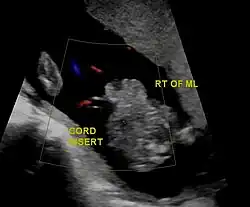

Diagnostic method | Ultrasound during pregnancy, based on symptom at birth[2] |

In the developed world, around 90% of cases are identified during normal ultrasound screens, usually in the second trimester.[17]